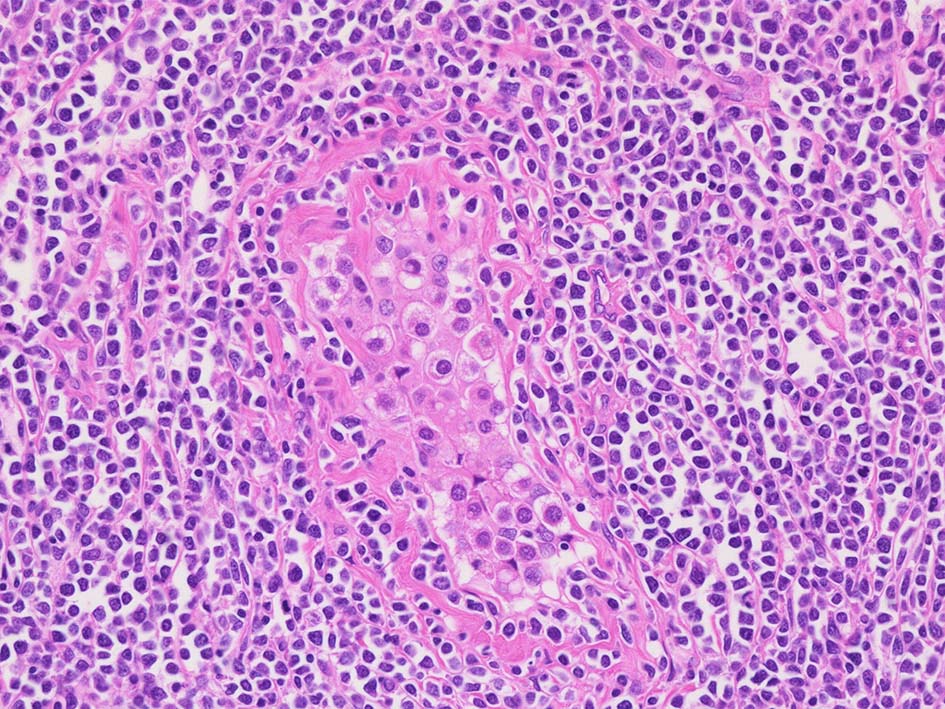

腫瘍内に壊死が認められる. 異型リンパ球の密な増殖により精細管は消失している.

腫瘍細胞はcentroblastic cells. mitosisやapoptosisが多い.

小リンパ球と同程度か1.5倍くらいのサイズ, round/ convoluted nucleiをもつリンパ球がシート状密に増殖する. 核クロマチンは粗で, 核小体が認められる核もある.

DLBCLとは細胞の大きさや細胞所見が異なっている. 精細管への浸潤, 占拠所見がある.